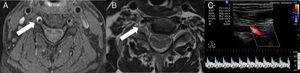

Fat-suppressed magnetic resonance imaging (MRI) of the neck showed a hyperintense crescent-shaped image in segments V1 and V2 of the right vertebral artery (Fig. 1) indicating an intramural haematoma secondary to arterial dissection. No relevant findings were observed in the brain MRI images; echo Doppler of extracranial vessels showed a biphasic flow in the V2 segment of the right vertebral artery. Pulsatility index was high but no intimal flap was detected.

Neck MRI axial images (A, B): fat saturated T1-weighted sequence (A) showing a hyperintense signal surrounding the right vertebral artery at the C5 level (arrow), which is compatible with intramural haematoma. The T1-weighted sequence (B) shows compression of the C5 root (arrow) due to expansion of the haematoma. Colour Doppler ultrasound of the extracranial portion of the right vertebral artery (C) shows a biphasic flow in the V2 segment and increased pulsatility. No flow is observed in segment V1.